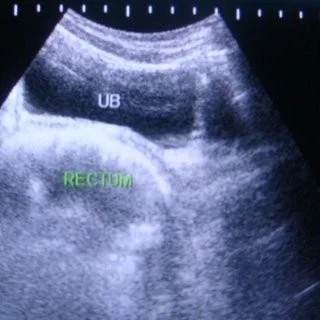

Ultrasonography

- Ultrasound is not substituting good history & a thorough examination.

- Always do an abdominal scan before using the vaginal probe.

Role of Ultrasound

- To examine the uterus, ovaries, cervix, vagina and adnexae.

Patient Preparation

- Scan the patient in the first 10 days of the cycle.

- Full bladder is required .(Abdominal US) Instruct the patient to drink 1 Litre of water.

Scanning Technique

Transabdominal

- Full bladder

- Panoramic view

For :

- large masses

- Abdominal organs

- Lymph nodes

Transabdominal Approach

This is a generalised overview to identify the cervix, uterus and ovaries.

- Check for the orientation the uterus (anteverted Vβs retroverted)